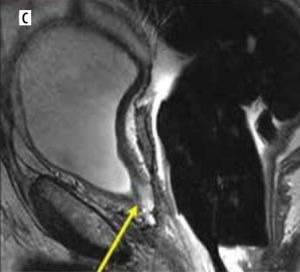

Figure 2

A 73-year-old male with post-prostatectomy with a false negative on axial 18F-fluciclovine-PET/CT (A) study indicated the absence of uptake in the surgical bed. Axial post-contrast T1-weighted (B) and sagittal T2-weighted (C) MRI images exhibit an intermediate T2 signal affecting the resection site of the prostate involving the left posterior anastomosis (arrows) (B and C). Further clinical and imaging follow-up and PSA monitoring confirmed the presence of disease recurrence